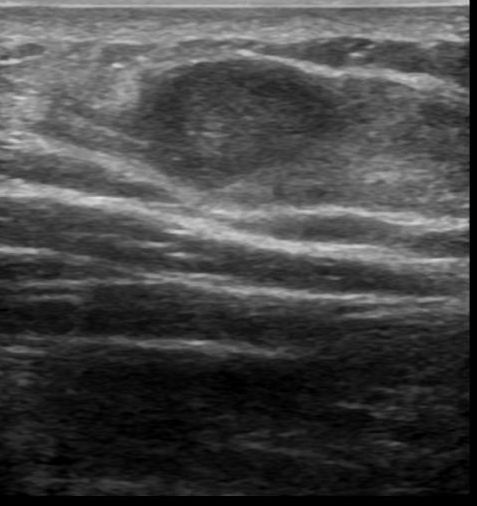

Lipoma | Radiology Key

Lipoma | Radiology Key

Lipoma | Radiology Key

Lipoma – subdeltoid | Image | Radiopaedia.org

Lipoma | Radiology Case | Radiopaedia.org

Lipoma | Radiology Case | Radiopaedia.org